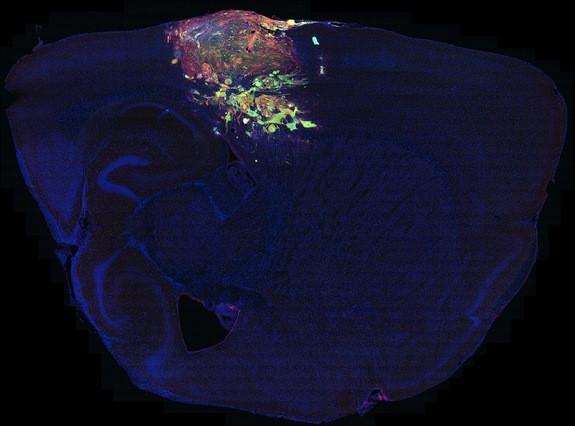

Cancerul (verde) se răspândește în creierul unui șoarece. Cercetătorii au raportat în revista Science pe data de 18 octombrie că modificările genetice ale celulelor canceroase le schimbă în celule stem, care se pot diviza continuu.

Un gliom (o tumoare primitivă, dezvoltată din celulele gliale), crescând în creierul şoarecelui.

Gliom (verde) transformându-se în celule stem (roşu).

O tumoare dezvoltându-se în creierul unui şoarece. Oamenii de ştiinţă spun că orice celulă a creierului poate da naştere unei tumori.

Glioblastoamele sunt cele mai agresive şi mai comune tumori ale creierului, cu o medie de viaţă e 14 luni de la diagnosticare. În imagine se observă cum cancerul se răspândeşte în creier.